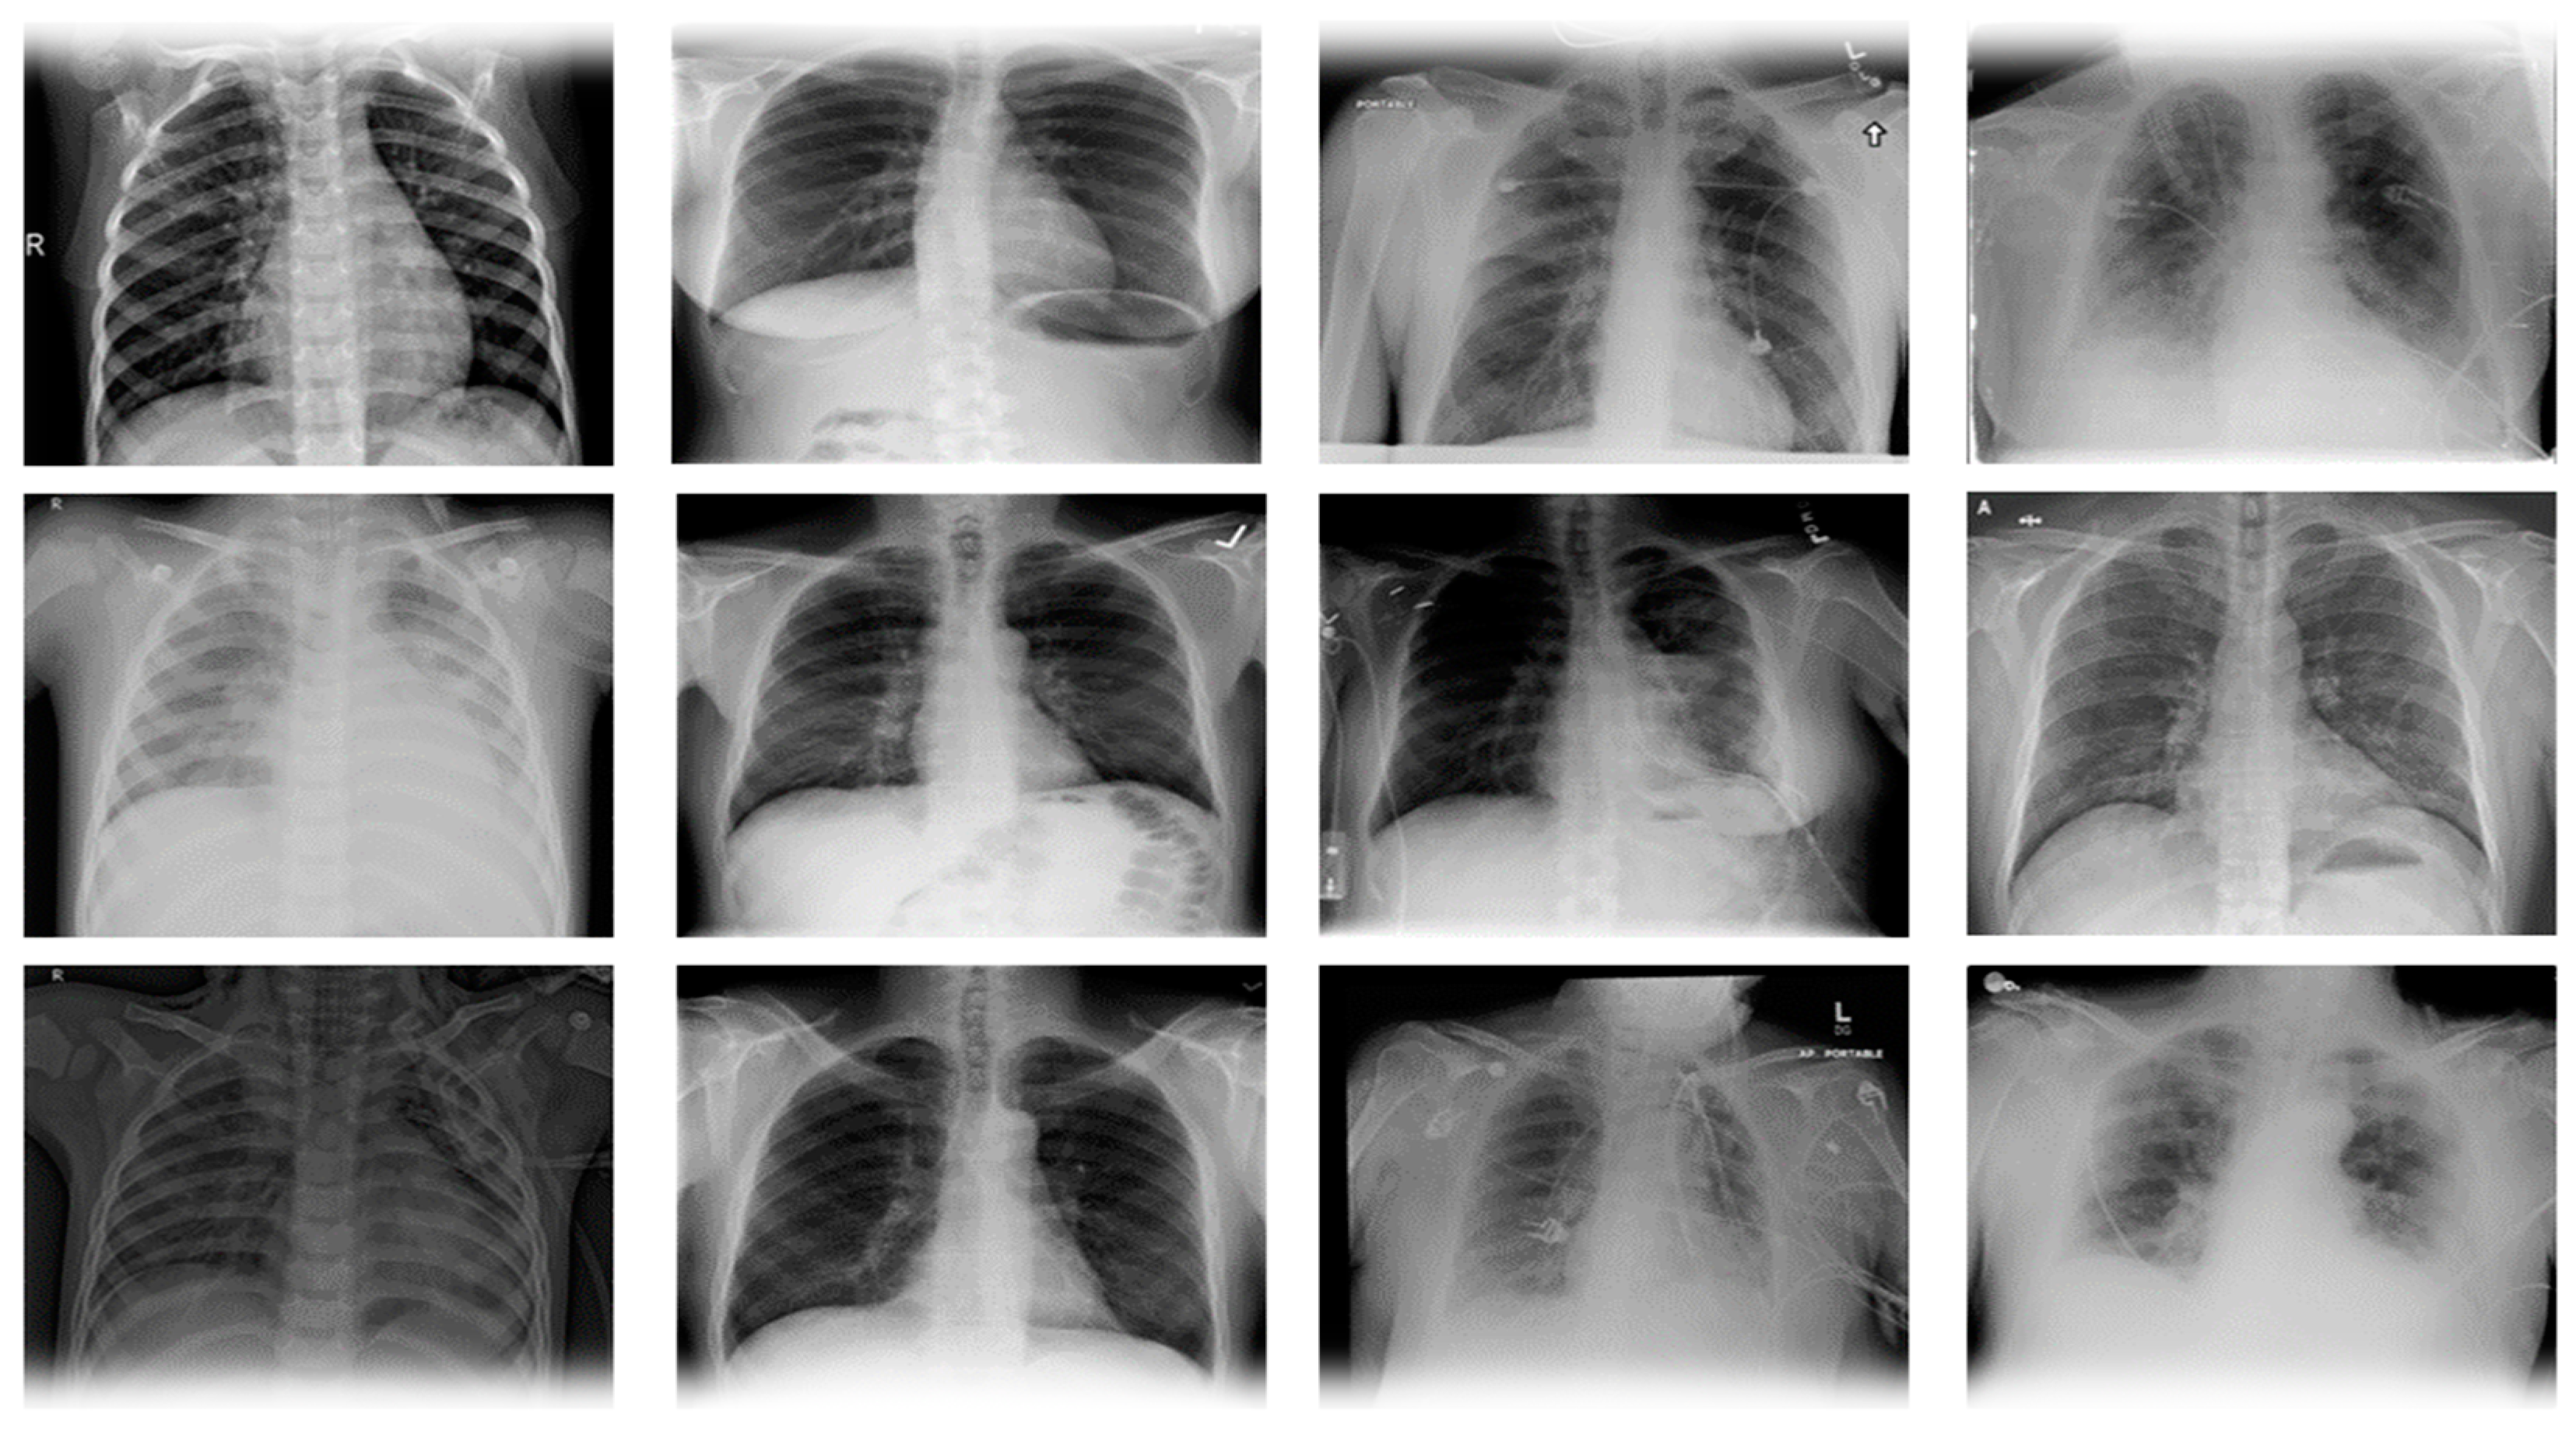

We employed the COVID-19 radiography images dataset [60,61] for the proposed CovidDetNet approach, produced by a group of academics from the University of Dhaka, Bangladesh and Qatar University, Qatar, to detect COVID-19. This COVID-19 chest radiograph image database is developed and created in collaboration with medical doctors containing COVID-19 positive samples, pneumonia, and healthy samples. The COVID-19 chest radiograph images database, which was recently released, includes 3616 chest radiographs of COVID-19 infected people, 10,192 chest radiograph images of healthy people, 6012 Lung Opacity, and 1345 images of pneumonia. The images in the dataset are 1024 × 1024 pixels in size. The images were resized to fit the need of each model. It is a standard Kaggle dataset that is freely available for research purposes. This dataset’s radiograph images are grayscale and have the exact dimensions. A few example image samples from the SIRM dataset are displayed in Figure 3, whereas Table 3 provides statistical information about the dataset.

Figure 3.

COVID-19 radiography database image samples, the first column have viral pneumonia, the second column has Normal, and the third column has lung obesity, whereas, the fourth column has COVID-19 chest radiograph images.